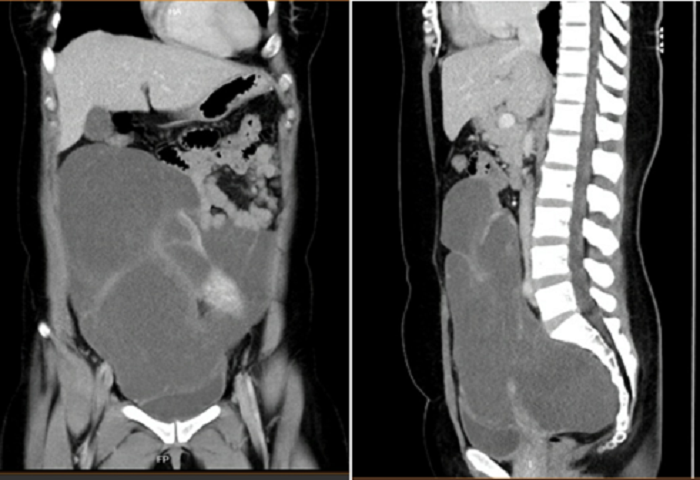

Qua thăm khám kết hợp với siêu âm, chụp CT, bác sĩ phát hiện chị A. có khối u rất lớn, chiếm hết 2/3 ổ bụng, chèn ép ruột, bọng đái, tử cung, buồng trứng, vách chậu và xương cùng lại len vào giữa xương cùng và trực tràng.

"Kích thước bướu là 20x30 cm, cân nặng 2,8 kg, mô bướu rất bở, dễ vỡ, len lỏi vào các cơ quan khác nên việc mổ cắt trọn u là việc rất phức tạp, khó khăn" - bác sĩ Nguyễn Triệu Vũ, Trưởng khoa Ung bướu, BV Quận Thủ Đức chia sẻ.

Ảnh chụp khối u mạch bạch của chị A.

Bằng sự tập trung cao độ, ekip điều trị đã tiến hành cắt hoàn toàn khối u, bảo vệ an toàn cho các cơ quan khác. Kết quả xét nghiệm cho thấy đây là khối u bạch mạch hiếm gặp, hình thành từ phát triển bất thường của hệ bạch huyết, thông thường u bạch mạch xuất hiện ở da, vùng đầu cổ, nách…

"Phần lớn khối u bạch mạch là lành tính và phát triển chậm, không gây triệu chứng, do đó có thể theo dõi không cần phẫu thuật. Khối u nằm sâu trong vùng chậu như trên là rất hiếm gặp" - bác sĩ Vũ phân tích.